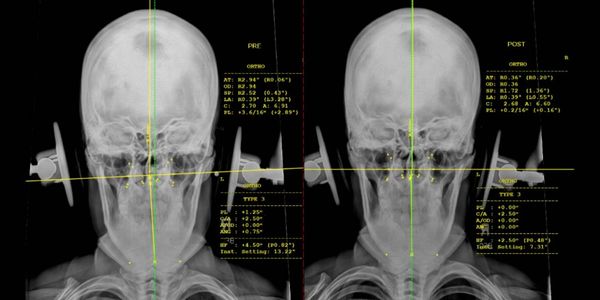

The only difference in addition to general Chiropractic, being the application and location of the alignment applied to the spine. Upper Cervical Chiropractors focus on the Atlas (C1) and the Axis (C2). The first two bones of the spine, under the skull.

The goal of Upper Cervical Care (UCC) is to improve brain-to-body connection, ensuring that the nervous system is operating at its best, specifically the autonomic nerve system in particular. Removing Vertebral Subluxations through spinal corrections affects the function of the entire body, allowing the body to heal more efficiently and function at it's optimum. Read more about Vertebral Subluxations in our TREATMENT tab above.

We practice Upper Cervical Chiropractic and activator techniques to align and correct the spine to regulate the nervous system and musculoskeletal system. Watch a video of the process of a Upper Cervical adjustment here: